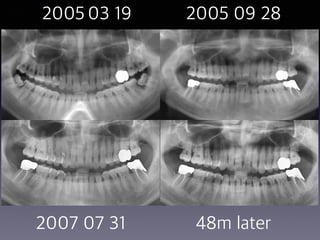

#31 partial pulpotomy

follow-up

(38 female)

2005 03 19 2005 09 28

2007 07 31 48m later